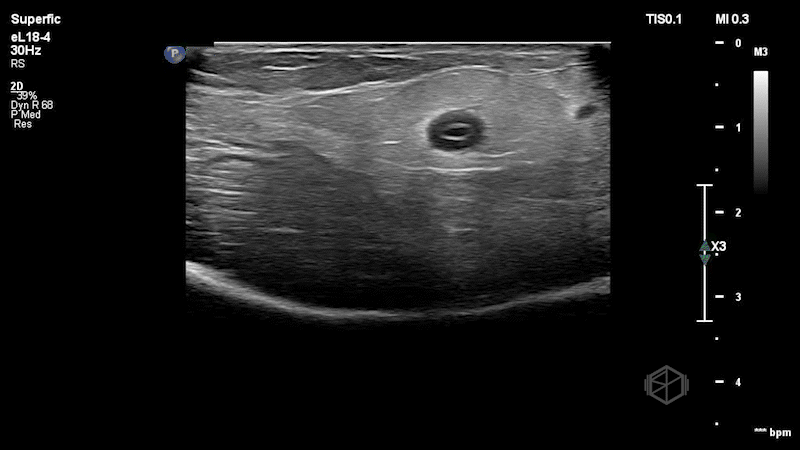

He performed a POCUS of the area that showed:

This patient has a basilic vein that has significant mural thickening with some echogenic material within the vessel in clip 2. It remains compressible. The patient was discharged with appropriate instructions. He later returned and was seen again by Dr. Gorynski a few days later for a similar complaint and had a radiology ultrasound (RADUS) that demonstrated chronic superficial thrombophlebitis involving the cephalic and basilic veins of the right upper extremity, but this visit took far longer than his first due to the RADUS.

Diagnosis: Superficial thrombophlebitis of upper extremity vein

• Normal veins demonstrate an anechoic lumen with a smooth wall and complete compressibility. On POCUS inflammation/edema of the vein can indicate phlebitis and presence of echogenic material within the vessel indicates thrombophlebitis (30171620).